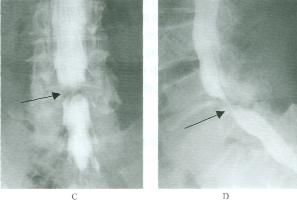

脊髓造影

-

椎管造影是判断腰椎管狭窄症的重要方法之一,其优点是在不同部位重复观察造影柱的形态、硬脊膜外间隙的宽度和硬脊膜囊前后径及横径、神经根鞘充盈程度,并与狭窄部位上下进行对比,有助于诊断狭窄部位范围及其程度。

腰椎管狭窄者椎管造影均有不同程度的造影剂充盈缺损,有的完全梗阻,完全梗阻断面常呈幕帘状、笔尖状,有的呈弹头状,有的呈毛刷样充盈缺损。部份梗阻表现在狭窄处呈点滴状,呈葫芦状。椎管造影在诊断腰椎管狭窄症中有重要价值。如能直接在透视下动态观察造影剂在椎管内流动的情况,通过多方面的检查,可显示椎管的全貌。摄正、侧位片和斜位片,造影可以明确显示硬膜囊和神经根袖的形态和位置的变化。

脊髓造影的诊断符合率为90%左右,但不能显示侧隐窝。对侧隐窝的狭窄诊断较准确的是CT。